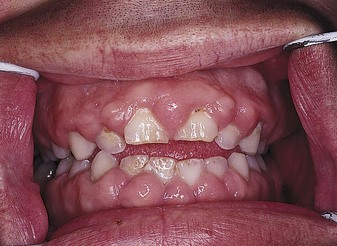

Restriction of physical activity is not necessary, but adult supervision during swimming or bathing is advisable. A family assessment is helpful in establishing rapport and setting realistic short- and long-term goals. Too much attention to seizures by well-meaning adults can make control difficult. The child may learn to use the threat of a seizure to manipulate caregivers. Teaching should include first aid treatment for seizures (see Table 23-2), the importance of compliance with long-term medication regimens, and general reassurance that the child can lead a normal life. Medications used in the treatment of epilepsy are outlined in Table 23-3. The gum hypertrophy (Figure 23-10) that occurs as a side effect of phenytoin (Dilantin) will require meticulous oral hygiene and special care, especially if orthodontic treatment is necessary. Death or serious injury rarely occurs from a seizure, and it does not cause mental deterioration. The Individuals with Disabilities Education Act (IDEA) guarantees children with disabilities the right to publicly financed educational programs in the least restrictive environment possible.

| Phenytoin (Dilantin) | Ataxia, insomnia, nystagmus, gum overgrowth, hirsutism (hairiness), rash, nausea, vitamin D and folic acid deficiencies | Generally effective and safe; may cause cognitive impairment; regular massaging of gums decreases hyperplasia; used in combination with phenobarbital. Intravenous (IV) doses should not be mixed with glucose solutions. |